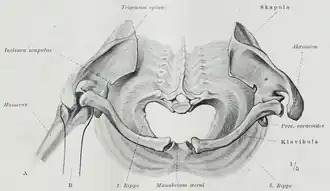

Superior thoracic aperture seen from above | |

The superior thoracic aperture is essentially a hole surrounded by a bony ring, through which several vital structures pass. It is bounded by: the first thoracic vertebra (T1) posteriorly; the first pair of ribs laterally, forming lateral C-shaped curves posterior to anterior; and the costal cartilage of the first rib and the superior border of the manubrium anteriorly.

The adult thoracic outlet is around 6.5 cm antero-posteriorly and 11 cm transversely. Because of the obliquity of the first pair of ribs, the aperture slopes antero-inferiorly.

The clavicle articulates with the manubrium to form the anterior border of the thoracic outlet. Above the superior thoracic outlet is the root of the neck, and the superior mediastinum is inferiorly related. The brachial plexus is a superolateral relation of the thoracic outlet. The brachial plexus emerges between the anterior and middle scalene muscles, superior to the first rib, and passes obliquely and inferiorly, underneath the clavicle, into the shoulder and then the arm. Impingement of the plexus in the region of the scalenes, ribs, and clavicles is responsible for thoracic outlet syndrome.